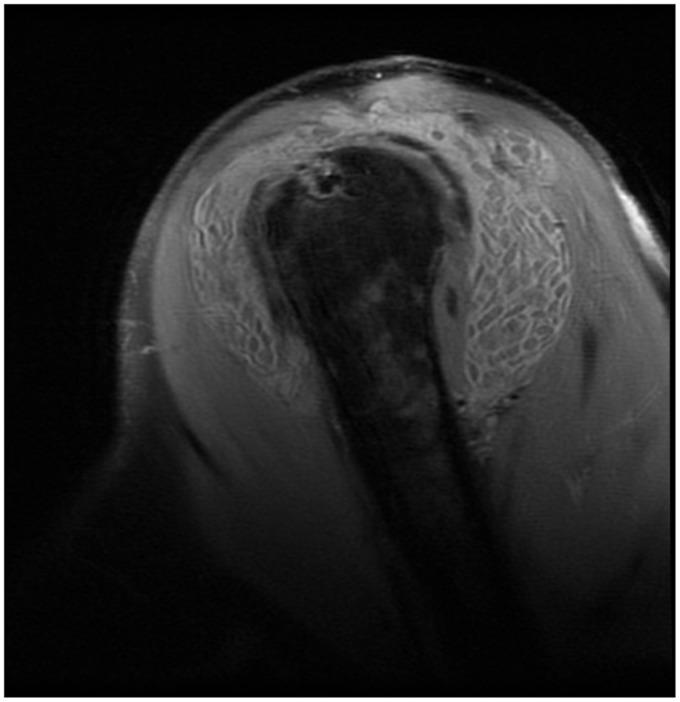

The Risotto sign - a severe inflammatory bursitis with rice body formation, complicating a rotator cuff repair with a bioabsorbable suture anchor.

There is an association between inflammatory bursitis with rice body formation and use of bioabsorbable suture anchors.